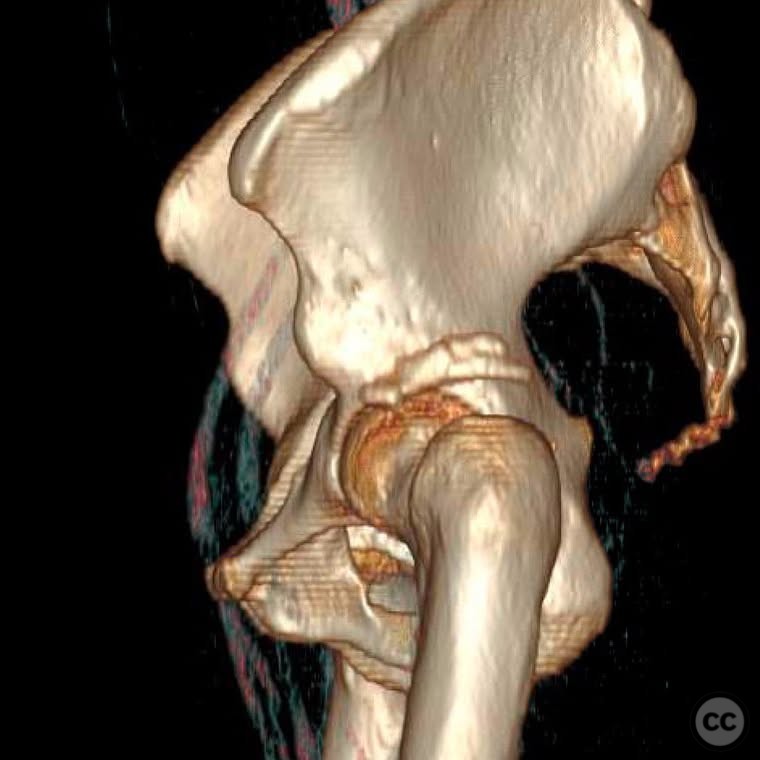

Clinical and radiological findings:  A 33-year-old female involved in a motor vehicle collision presented with a posterior hip dislocation accompanied by a comminuted supra-foveal femoral head fracture, a cranial peripheral posterior wall fracture, and a non-displaced femoral neck fracture. The injury is associated with a risk of sciatic nerve palsy and avascular necrosis (AVN).

Planning remarks:  The preoperative plan involved a Gibson approach with a trigastric slide osteotomy for anterior dislocation to address the femoral head fracture. The intention was to reconstruct the femoral head using a femoral head allograft due to a 20% pie slice defect. The posterior wall was to be addressed through capsulolabral repair with suture anchors and spring plates.

Anatomical surgical approach:  A Gibson approach was utilized, involving a trigastric slide osteotomy to achieve anterior dislocation of the hip. This allowed access to the femoral head for reconstruction using an allograft. The posterior wall was accessed for capsulolabral repair.